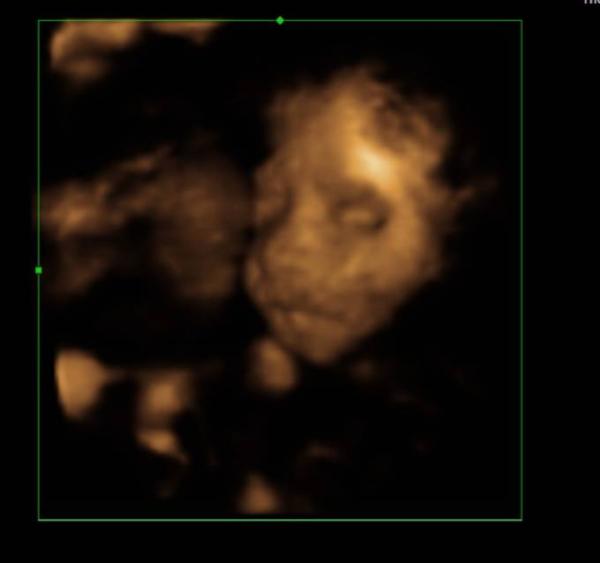

So hier das 3d Bild von heute, ich liebe sie so sehr

Oooh sie sieht so brav aus

Das Foto ist wunderschön

Schön das alles so gut ist! Das Bild ist echt süß, finde das Gesichtchen sieht richtig nach Mädchen aus irgendwie